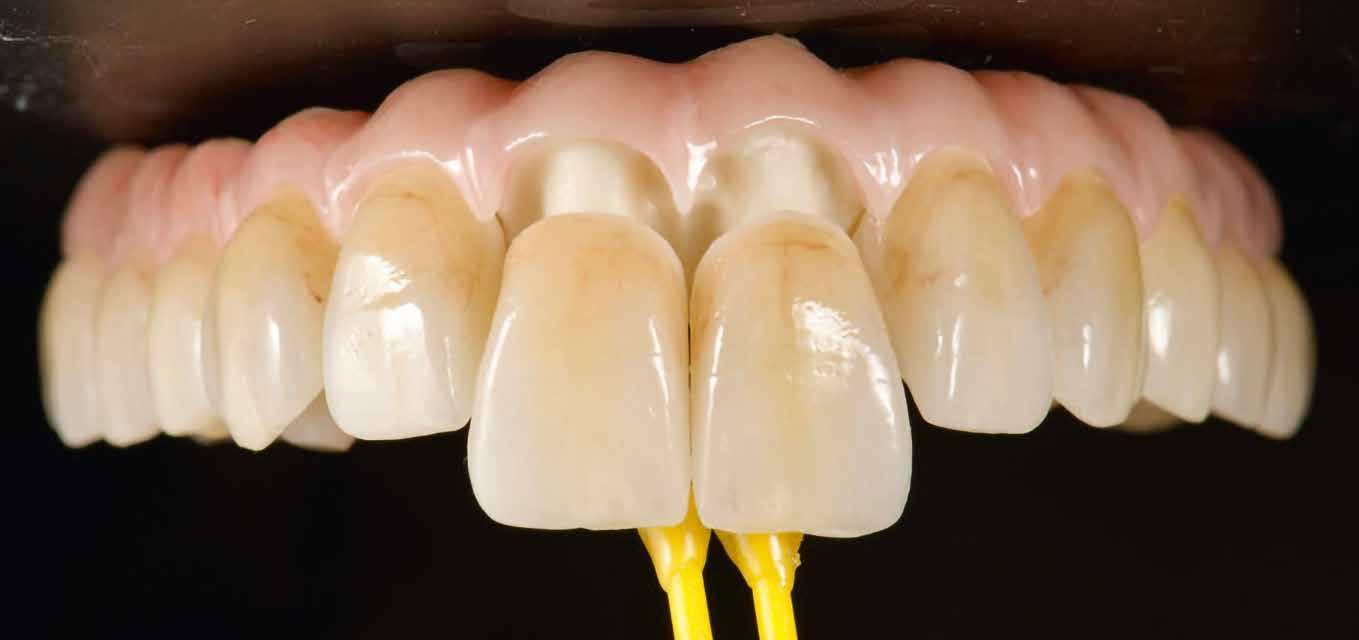

3. kép: Új teleszkópos fogpótlás az 16, 15, 13, 23 és 27 fogakra.

Teleszkópos munka, élő eset bemutatásával ismertetem, mi az, ami már lehetséges. A munkaasztal-szkenneren kívül bevetésre került a digitális munkafolyamatok során egy intraorális szkenner (IOS) is. A 3D nyomtatású testek gyártása a laboratóriumban LCD- és DLP nyomtatókkal történt. A fémes komponenseket szelektív lézerolvasztásos (SLM) technológiával készíttettük.

• új, teleszkóp-elhorgonyzású felső fogpótlás az 16, 15, 13, 23 és 27 fogak felhasználásával (3. kép)

A digitális lenyomatvételt (4. kép) követően a primer részek előállításához a CAD szoftverben vágatlan fogívet szegmensekre osztottuk, és a pontosság ellenőrzésére csonkokat generáltunk (5-6. képek). Az ebből nyert STL-adatállományt virtuálisan illesztettük a 3D nyomtató építőasztalára (7. kép), és a Bego cég VarseoWax Model segítségével Anycubic Photon Mono X LCD-nyomtatóval kinyomtattuk a mintákat (8. kép)

A 0°-os, egymással szemben legalább két 3 mm-es magasságú felületet felmutató primer koronákat ismét a CAD szoftverrel terveztük meg (9. kép). A gyártás a Bego CAD/ CAM gyártóközpontjában, Brémában, SLM-eljárással történt, Wirobond C+ (Bego) ötvözetből.

A lenyomatkanál (11. kép) Varseo S DLP-nyomtatóval készült, VarseoWax Tray (Bego) anyagból, nyomtatva (12. kép)

A közben megérkezett primer koronák a minta csonkjaira voltak passzíthatók (13. kép)